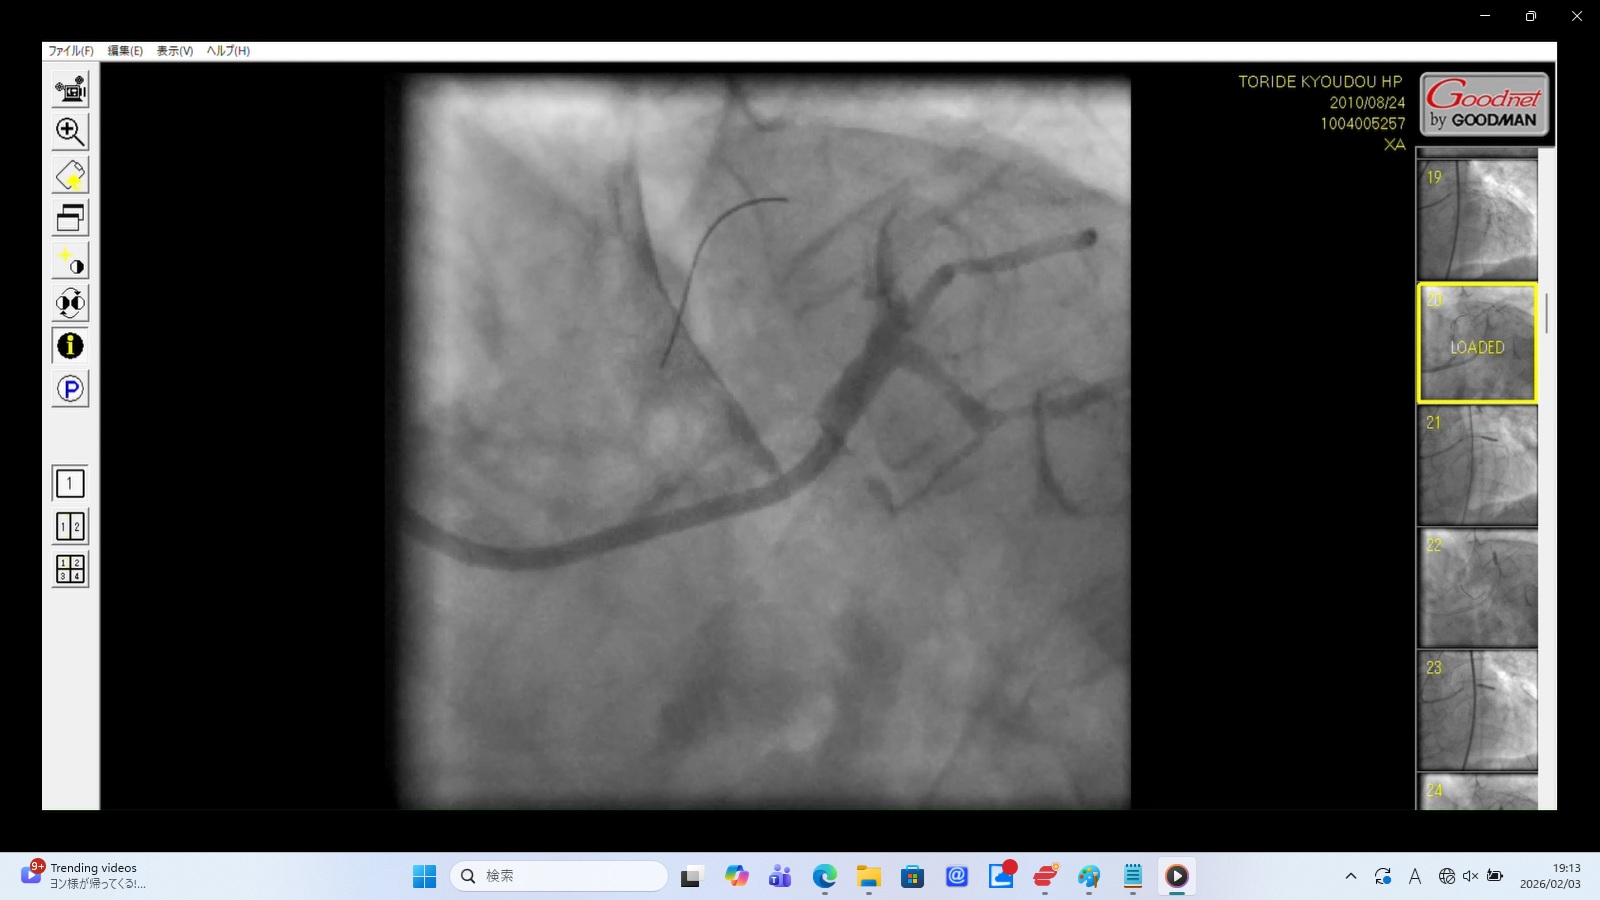

LMTからの漏出: カテーテル先端付近の左冠動脈主幹部において、造影剤が周囲に滲み出すような所見が認められる。これはカテーテル操作による主幹部損傷を強く疑わせる。

カテーテル先端の「血流なし」: 挿入部に流れが確認できないのは、カテーテル先端が血管の「真腔」ではなく、血管壁の層間(偽腔)に迷入してしまっている可能性を示唆する。

ゆっくり流れるLAD(偽腔の拡大): 通常、血流(造影剤)は冠動脈末梢まで瞬時に流れるが、ここでは末梢まで時間をかけて少しずつ流れていく。医原性冠動脈解離によって生じた「偽腔」に造影剤が入っていく時の典型的な見え方である。リアルタイムに剥離(解離)が進み、偽腔が広がっていくプロセスを捉えていると考えられる。